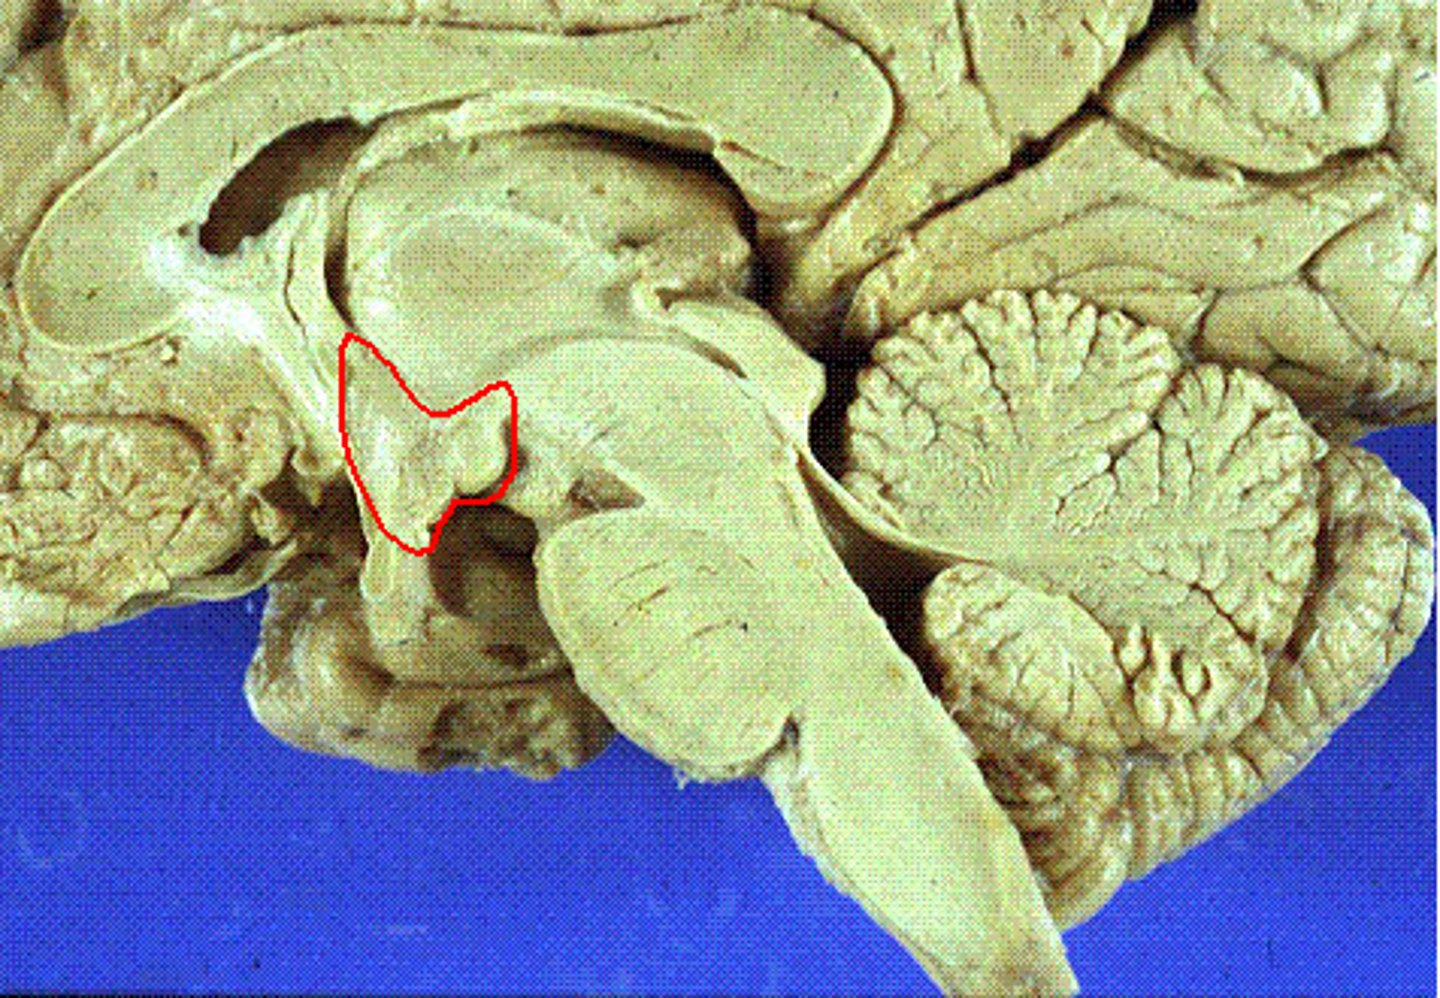

Thalmus

Part of the limbic system which receives sensory information such as vision, touch, audio, and sends it to the appropriate lobe for processing. Ex: Routing visual data from the eyes to the occipital lobe.